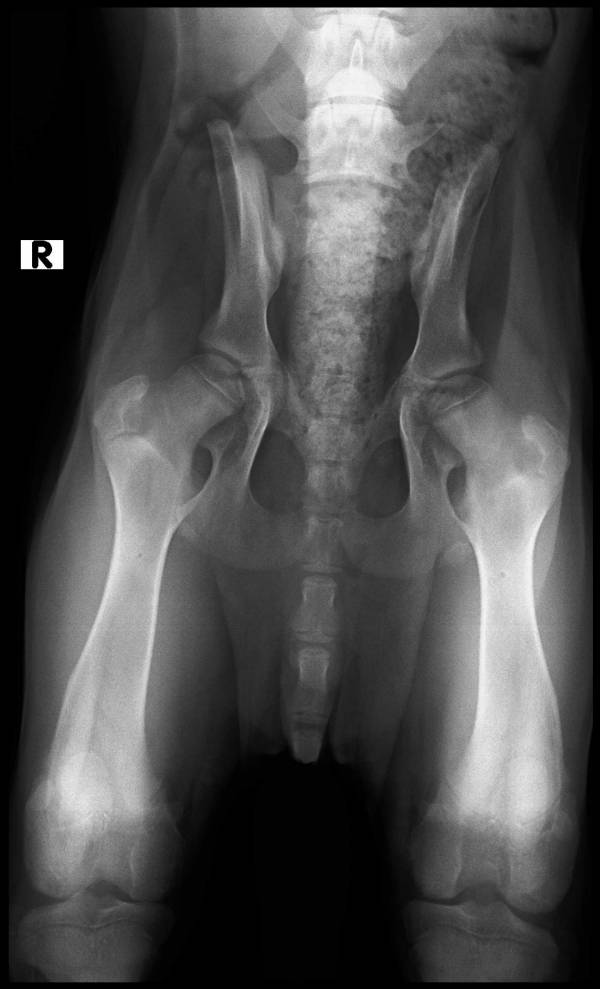

Here are Cheuui's exrays from Dr. Collins a well renown Vet in Efom for OFA...hip exrays...HE took them without sedation and Cheuui was a great boy and he said he was one fine boy

THE sockets are very deep and well formed, the growth plates are in very good pattern for his age and the ends and the dimensions of both sides is correct and even..

HE sees very good hips on the way to being produced if Cheuui eats properly and is kept from jumping from any heights and not slipping or being worm by over training concepts.

HE has no hip dysplasia..but he can develop environment problems if the dog is not cared for properly, exercise properly and with care to make sure he does not injure or wear his joints to a point it creates problems

Cheuui will be DM tested at the time he gets his OFA PRELIMS and tatooed at 13 months

Confused about what? Dr Collins preliminary xrayed Yellow Rose's puppy and thinks his hips look normal for breed and age. Fawndallas is sharing that news with us because Yellow Rose can't.